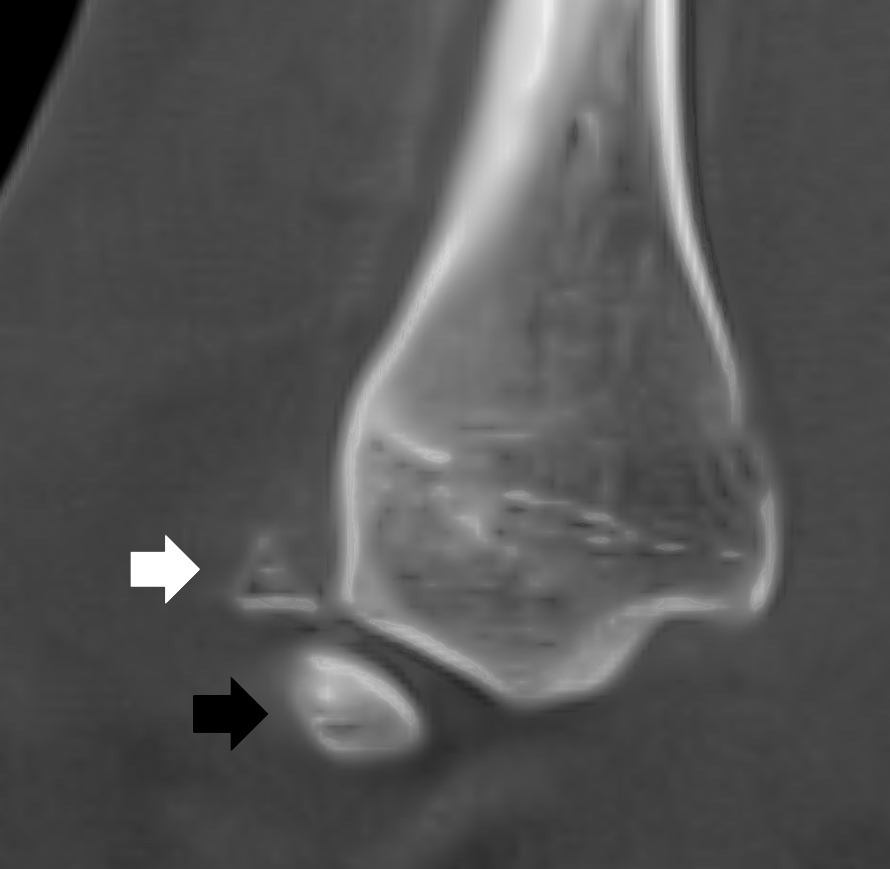

Home Schwerpunkte Krankheitsbilder Bänderriss am Sprunggelenk – exzellente Ergebnisse mit der richtigen Behandlung Kombination aus frischer Verletzung der distlen Fibula und os subfibulare

Kombination aus frischer Verletzung der distlen Fibula und os subfibulare